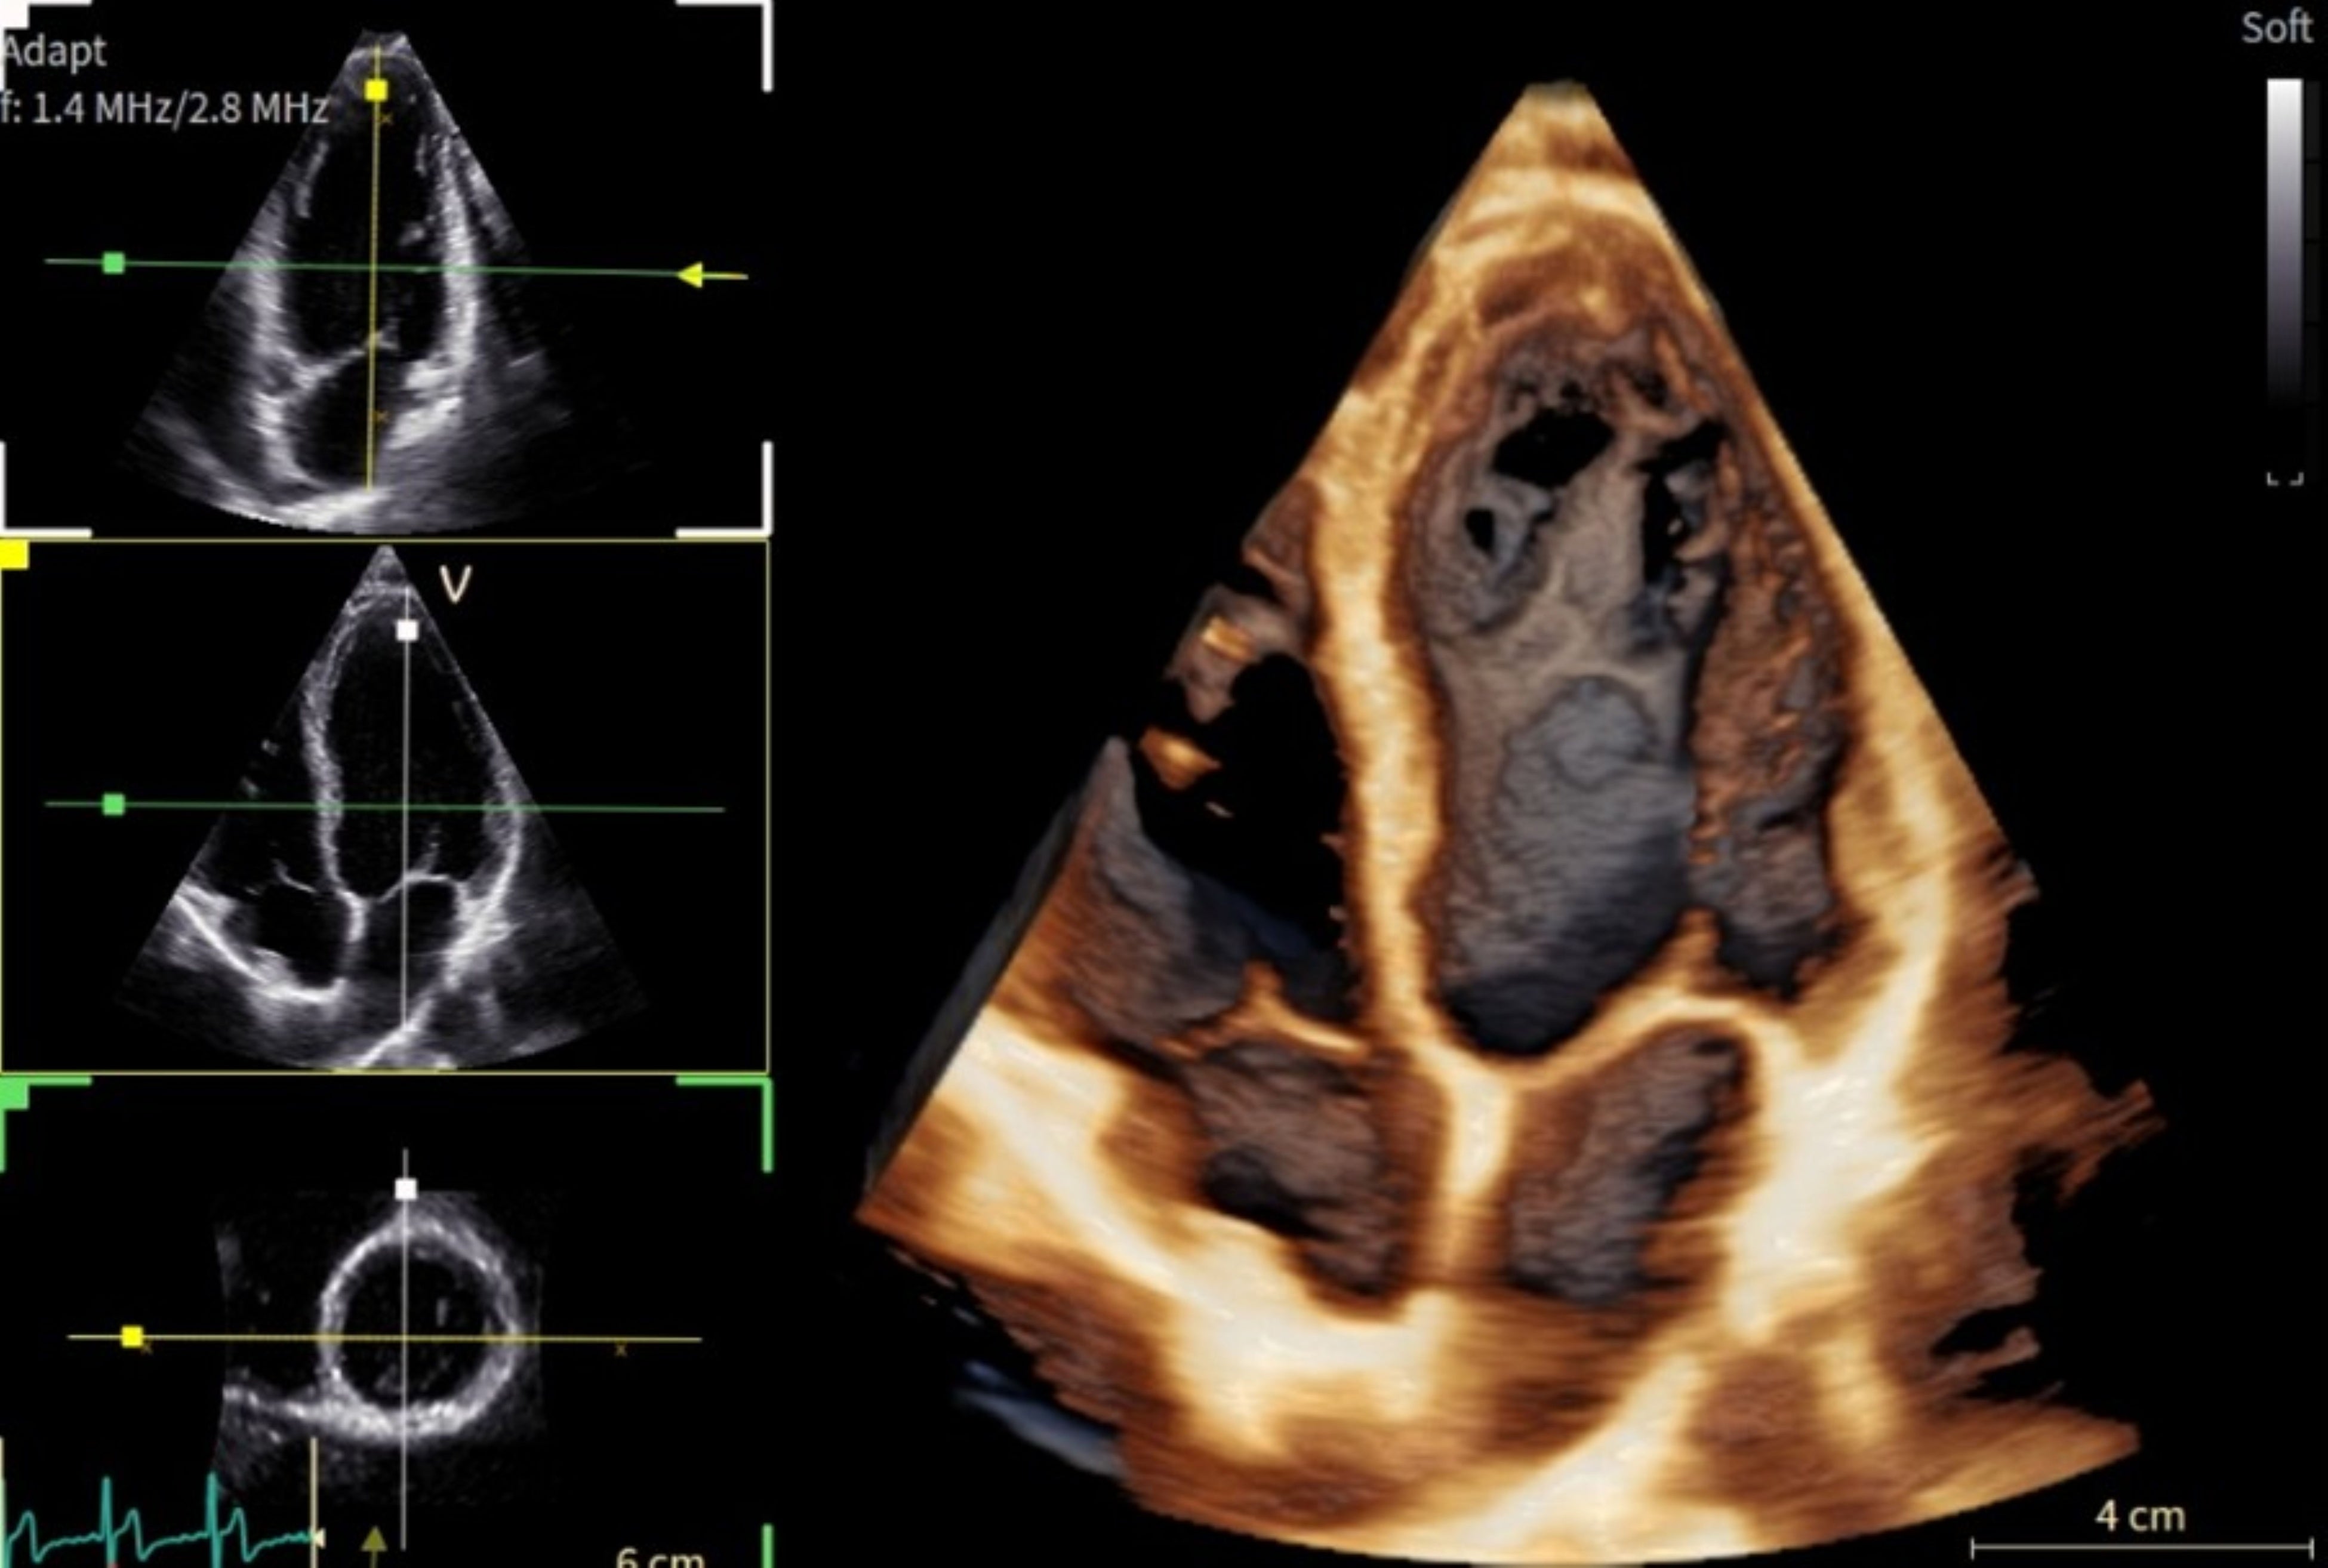

「Vivid Pioneer」は、これまで検査者が手作業で行っていた血流解析をAIが自動で行い、短時間で安定した測定プロセスを提供します。また、心臓の主要な部位(左心室と左心房)の動きや形を三次元で自動分析し、検査者間の標準化を支援します。そのほか、次世代の画像エンジン機能により、細部の見やすさ(空間分解能)や色の見やすさ(カラー感度)が向上し、より高精度な心臓の立体画像を描出します。